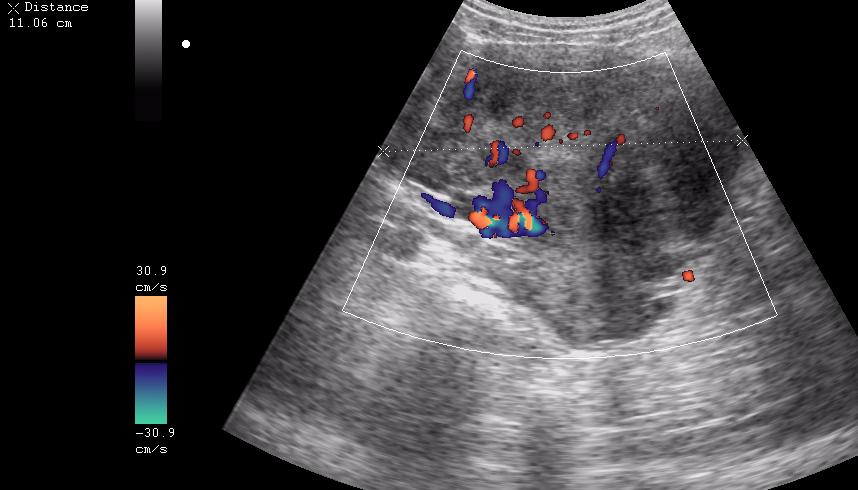

ну вот куда здесь ставить бодимаркер и какой?

31249.JPG

31416.JPG